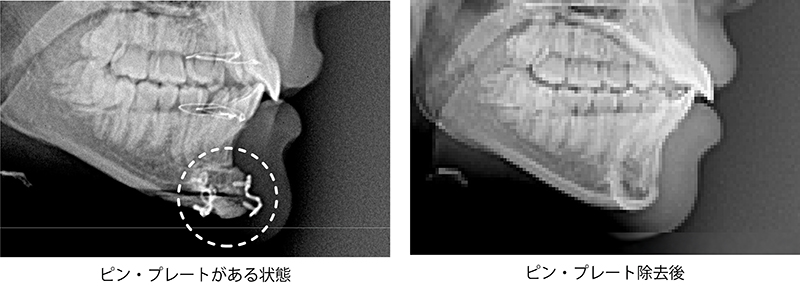

輪郭手術後のピン除去治療とは、顔面輪郭手術の際に使用した固定ピンやプレートを除去する施術です。輪郭手術で使用するピンやプレートは身体に安全な医療用の器具を使用しているため、本来であれば除去する必要はありませんが、「異物が体内に残るのが不安」「レントゲン撮影の際にピンやプレートが映ってバレるのを避けたい」といった理由で抜去を希望される方が一定数おられ、このような際に本施術が有効となります。当院で施術を行った方はもちろん、他院や海外(韓国など)で輪郭手術をされた方についても対応していますのでお気軽にご相談下さい。

輪郭手術後の固定ピン除去とは、正式な医学用語では抜釘術(ばっていじゅつ)と言い、両顎手術や輪郭整形後に骨に埋め込まれた固定ピンやプレートを除去する施術になります。

輪郭手術で使用する固定具はいずれも医療用として認可されており、心臓手術や歯科治療などで日常的に使用している器具のため本来は抜去の必要はないのですが、患者様によっては「輪郭手術を行ったことをできるだけ周囲にバレないようにしたい」「レントゲン検査で金属が映らないようにしたい」という方もおられ、このような際にピン・プレート除去の手術を行っております。

なおこの施術は「ピン除去」と言われることが多いですが、実際に抜去手術で取り除くものは、輪郭手術で骨切りをした際に骨を固定する際に止める金属製のプレート、スクリュー、ワイヤーとなり、「ピン」という道具は使用しておりません。ただ、韓国の美容クリニックの影響などもあるのか俗称として輪郭手術後の抜釘術を「ピン除去」と呼ぶことが多いため、このページでも分かりやすいように「ピン除去」という施術名で統一します。

- 輪郭手術後のピン除去では両顎手術や頬骨整形の際に挿入した金属プレートやワイヤー、スクリューなどの固定具を除去することができるため、それ以降で行うレントゲン撮影などでは金属が一切映らなくなるというメリットがあります。出来るだけ手術をしたことをバレないようにしたい、また異物が体内に残っている状態に違和感があるという際には、ピン抜去手術が有効です。